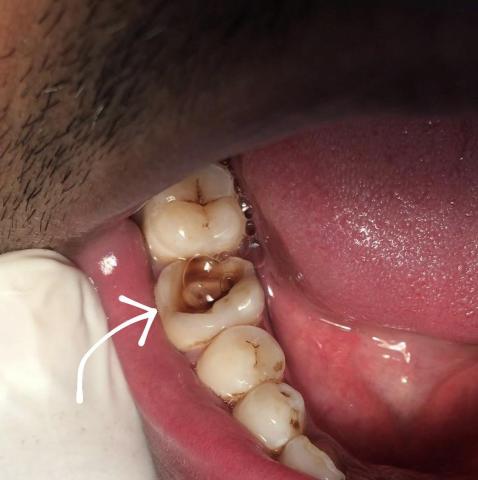

Part 1: Deep Caries / Irreversible Pulpitis Diagnosis (Image 1)

The first image clearly shows a molar (likely the second molar) with extensive tooth decay.

| Location | Lower right quadrant, second molar . | Deep Caries leading to Irreversible Pulpitis (severe, non-healing inflammation of the tooth nerve). |

| Appearance | Large, deep, dark brown cavity on the chewing surface (occlusal) and side (buccal/lingual) of the tooth. The cavity appears to extend deep into the dentin, possibly reaching the pulp chamber (nerve). | The decay has likely reached the dental pulp (nerve and blood vessels), causing infection. Symptoms would include spontaneous, throbbing pain, pain lasting after hot/cold exposure, or pain on biting. |

| Treatment | The tooth is unlikely to be saved by a simple filling. It requires either Root Canal Treatment (RCT) followed by a dental crown, or Extraction if the tooth structure is too compromised. | RCT aims to clean out the infection and save the tooth. An Extraction is the last resort. |